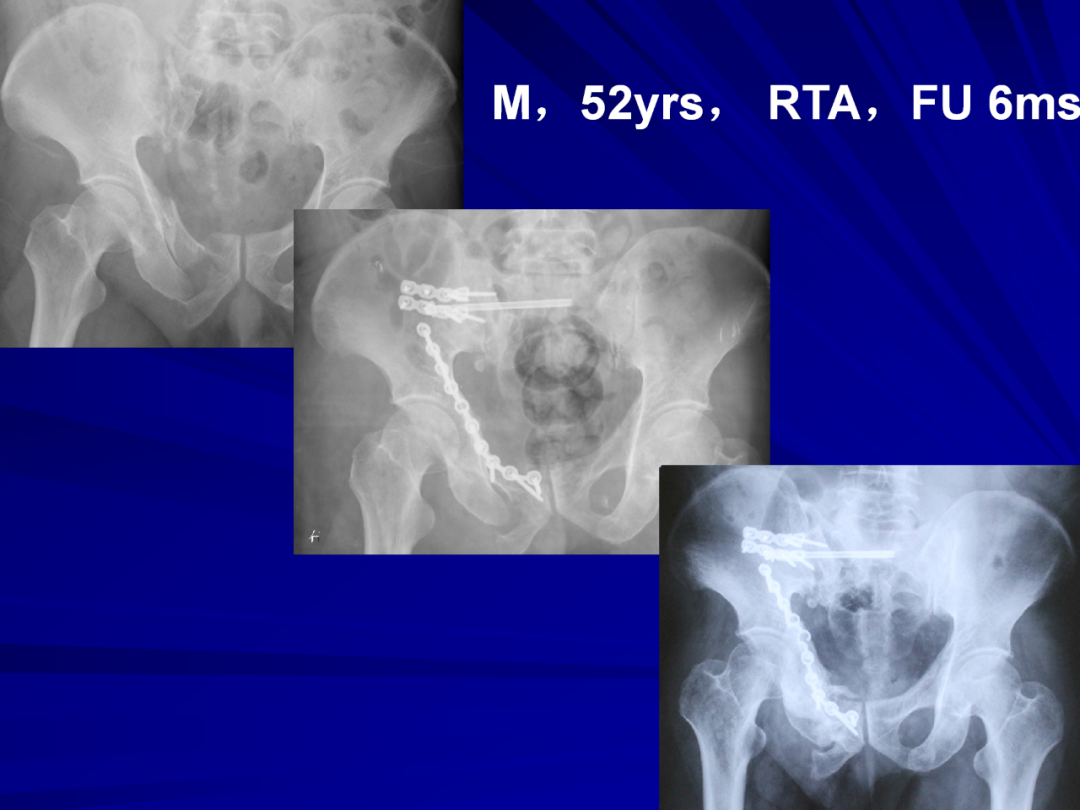

364例复杂骨盆骨折带你掌握内固定技术!